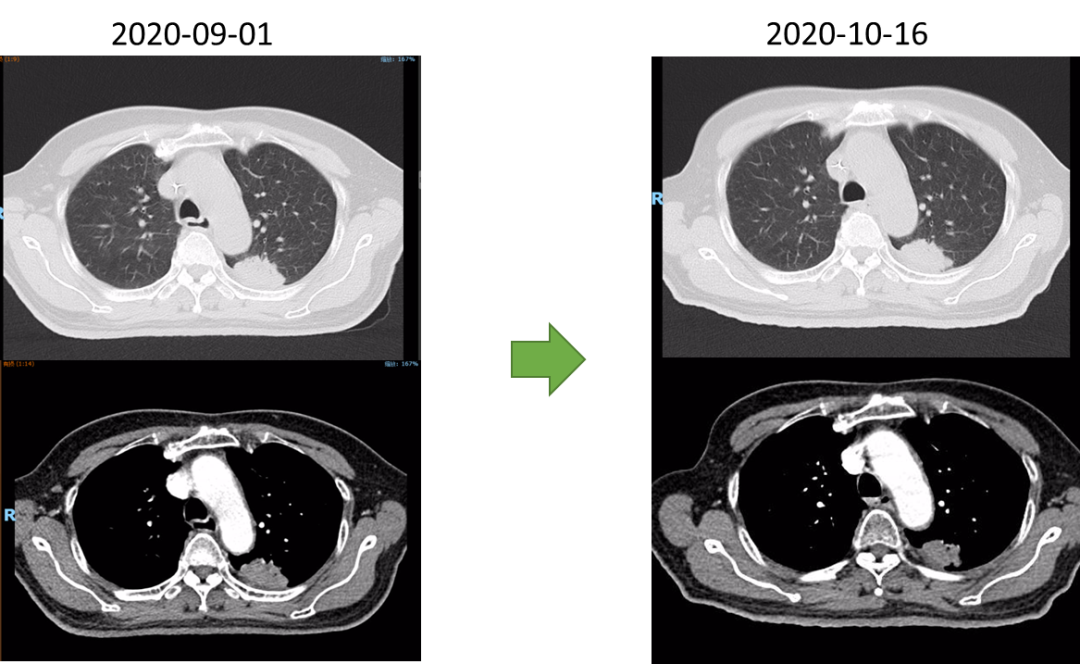

2020-08-27行放疗CT定位。2020-09-07~2022-10-23行肺部、食管放疗。

放疗同期行同步化疗+靶向治疗,具体方案为:洛铂50mg d1 q21d+尼妥珠单抗400mg Qw。放化疗前开始行重组人血管内皮抑制素(恩度)30mg d1-7q3w抗血管靶向治疗。放化疗结束后给予抗血管靶向及针对肺原发灶TKI靶向治疗维持,TKI靶向:克唑替尼250mg Bid po Qd。治疗后3个月,患者拒绝继续恩度靶向治疗。治疗后6月患者拒绝克唑替尼治疗。考虑肺癌为驱动基因阳性型,未能行食管癌治疗后免疫治疗维持。

疗效评估及随访

放射治疗结束复查胸部CT:左肺上叶尖后段与左肺下叶背段交界处病灶较前略显缩小,现最大横断面约2.6*2.8厘米,边缘可见毛刺,增强后可见强化,邻近胸膜稍增厚。食道中段管壁增厚,上下累及约4.5厘米(约胸5/6椎间隙水平至胸8椎体上缘水平),增强后强化程度似较前有所减低,隆突下见境界不清淋巴结。

2021-10-28外院PET-CT:原食管胸下段管壁高代谢灶较前缩小,放射性较前减低,现大小约15×17×17mm,SUVmax 3.1,考虑为治疗后改变。左肺上叶团块状高代谢灶较前缩小,放射性摄取较前减低,现大小约25×18mm,SUVmax 2.1,考虑为治疗后改变。

2022-03-28 PET-CT:1、食管癌放化疗后,食管胸中段管壁不规则增厚伴结节状代谢增高,与上次(2021-10-28)PET/CT检查对比,病灶代谢较前明显增高,考虑为肿瘤复发病灶。2、左肺癌放疗后及靶向药治疗后,原左肺上叶团块状高代谢“肿瘤灶”,现范围较前稍缩小,代谢较前稍减低,考虑为治疗后改变(肿瘤完全活性受抑,伴少许炎性反应可能)。